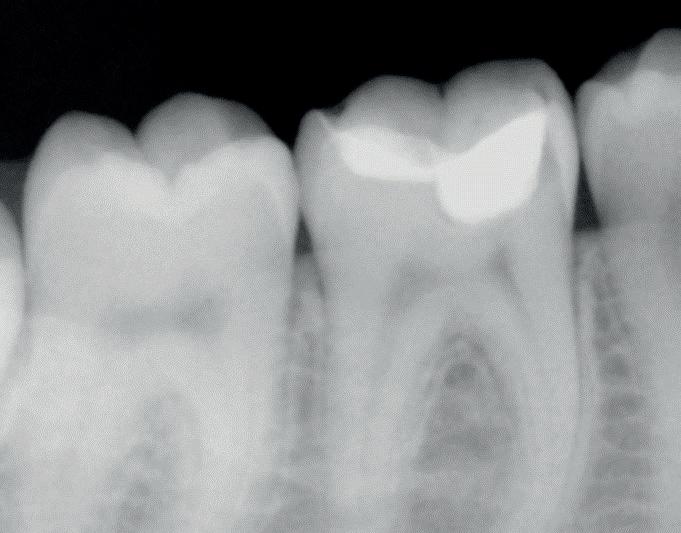

Predictable management of a deep carious lesion, page 27